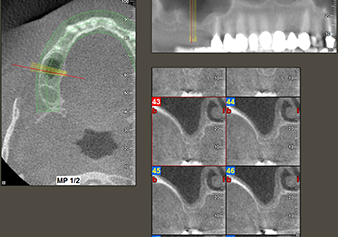

A 49-year-old female patient, a non-smoker and with nothing remarkable in her general medical history, was referred to our oral surgery practice for surgical extraction of tooth 16 and subsequent implantation. After the extraction, the patient experienced mild sinusitis trouble with the resultthat we initially waited six months before carrying out the measure. The residual bone height at the planned implant position measured 3-4 mm (Fig. 1 and 2).

To move the augmentation material in the direction of the maxillary sinus atraumatically, the implant was inserted very slowly by hand (Fig. 9). In the process, the membrane was pushed in the cranial direction once again. After two months, the surgical site healed without irritation. Six months later, the x-ray check showed a significant increase in opacity as an indication of ossification (Fig. 10). The prosthetic restoration was carried out with a metal-ceramic crown.